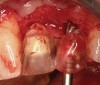

Figure 2  (Case 1) Condition of implant at surgical exposure.

Figure 2

Figure 3  (Case 1) Removal of implant was accomplished using piezo-surgery in order to maintain the lingual plate. Note that trephines are not recommended for this procedure.

Figure 3

Figure 4  (Case 1) Implant removed and lingual bone maintained to receive augmentation.

Figure 4

In evaluating the options, it was decided that the implant placed was too large and that the deciduous cuspid site could be used for a single implant as an abutment for a cantilevered pontic to restore the missing lateral incisor in a more esthetic manner. The goal the treatment was to augment the lateral incisor site in order to bring the facial tissue level more coronal (Figure 2 through Figure 11).